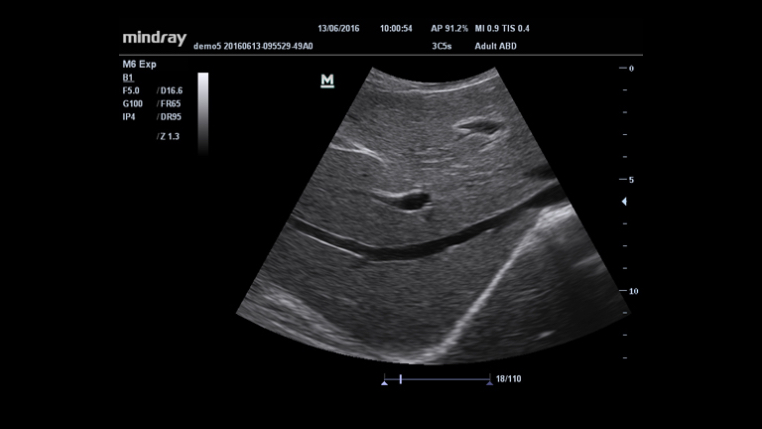

Formación de varios haces

iClear? (Toma de imágenes con supresión de manchas)

iBeam? (Toma de imágenes de composición espacial)